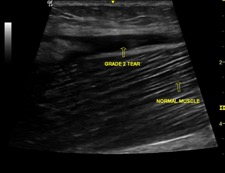

If there is a lot of bruising within 72 hours then it is advisable to get a scan on the injury in order to accurately diagnose the grade of tear and predict the likely time out of sport. Ultrasound scans are excellent for detecting muscle tears and can help predict return to play times. Below is the image of a grade 2 hamstring tear as was seen in this case study.

In the case example shown above I expect this elite sprinter to return to sport in 6-8 weeks. We will be closely monitoring the muscle recovery with ultrasound imaging to determine when it is safe to return to sport.

- Not getting the tear properly diagnosed. Muscle injuries can be effectively diagnosed and monitored with ultrasound scans and are much more cost effective than MRI scans. Ultrasound scans can also be used to determine when an athlete can safely return to play.